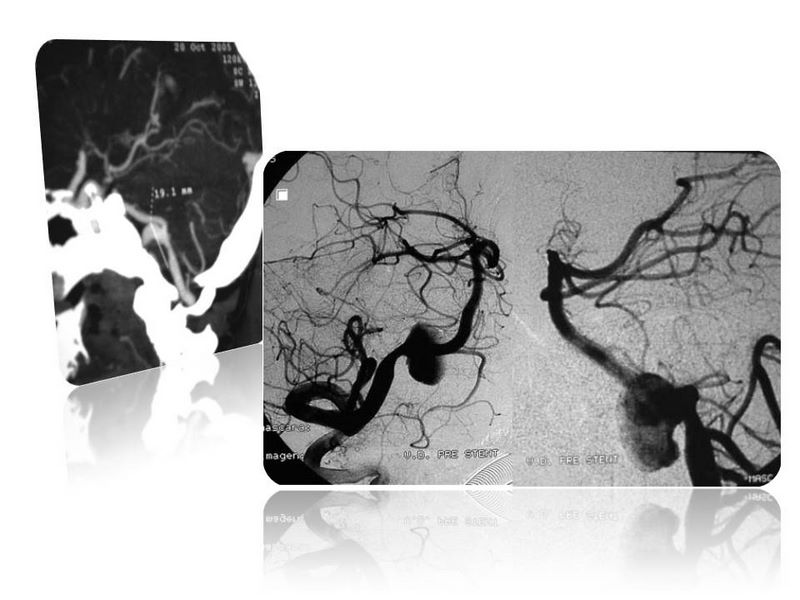

Aneurismas grandes